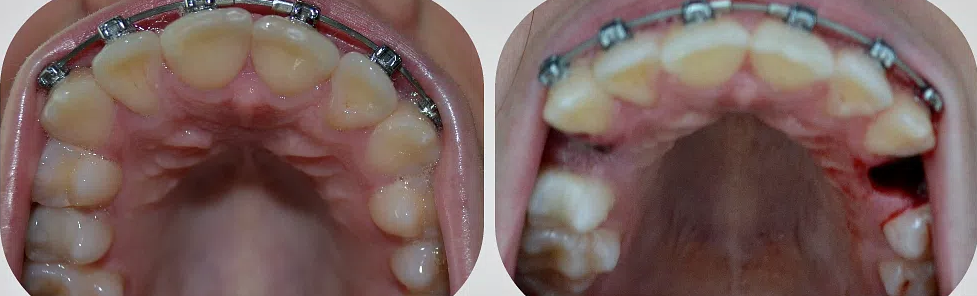

Сложное удаление зуба мудрости: фото до и после

Сложное удаление зуба предваряется проведением качественного рентгеновского обследования, поскольку восьмерка часто имеет искривленные корни, которые могут создавать трудности во время операции. Кроме того, ее корни часто становятся очагом воспаления, если при экстракции зуба загнутые кончики отламываются и остаются в толще кости.

Рентгеновский снимок перед процедурой сложного удаления зуба мудрости позволяет увидеть количество и строение корней восьмерки. Это гарантирует, что при поочередном извлечении частей зуба в кости не останется корней или их обломков.